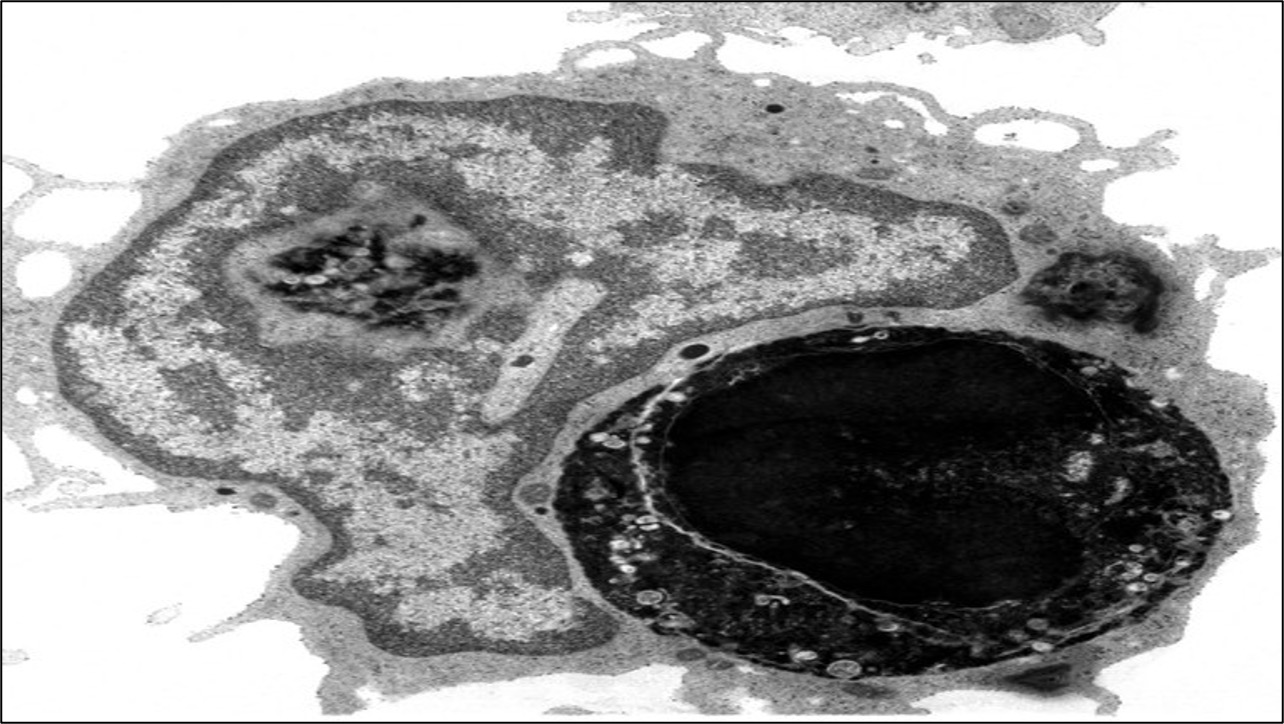

Pathogens are engulfed when cellular extensions (pseudopodia) surround the pathogen and then fuse to form an internal vesicle (endocytosis)

The vesicle is then fused to a lysosome (forming a phagolysosome) and the pathogen is digested by enzymes within the lysosome